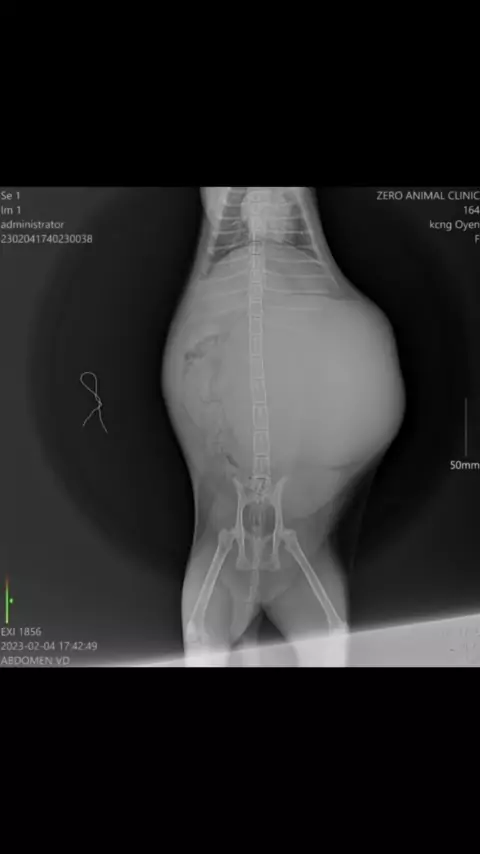

Alhamdulillah Masyaallah sebuah perjuangan panjang yg telah oyen lalui Oyen di temukan dalam kondisi perut besar berisi cairan Setelah dilakukan pemeriksaan dokter menyatakan oyen terinfeksi virus FIP (feline infectious peritonitis) yaitu virus corona pada kucing yg bermutasi menjadi FIP Setelah dilakukan pemeriksaan (mXray) oyen jg harus dilakukan sedot cairan Cairan yg berhasil dikeluarkan berwarna merah gelap sebanyak 1,5 litter Lalu utk pengobatan oyen menggunakan obat injeksi dari Bas...